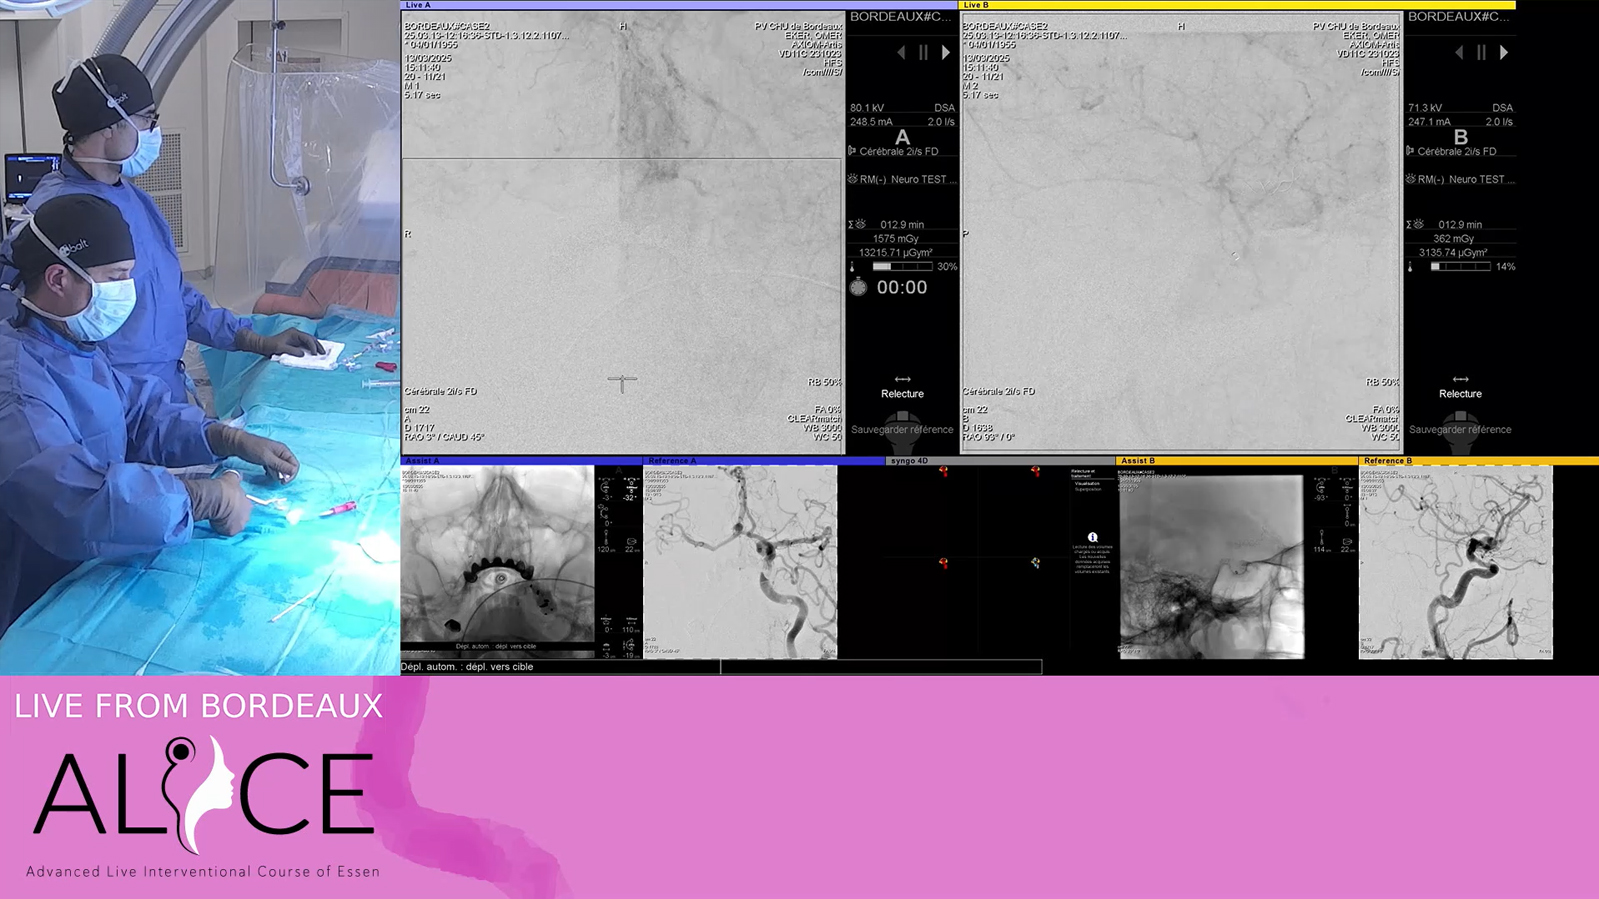

from Bordeaux: a "sequenced" coiling to adress a multilobulated complexe intracranial aneurysm